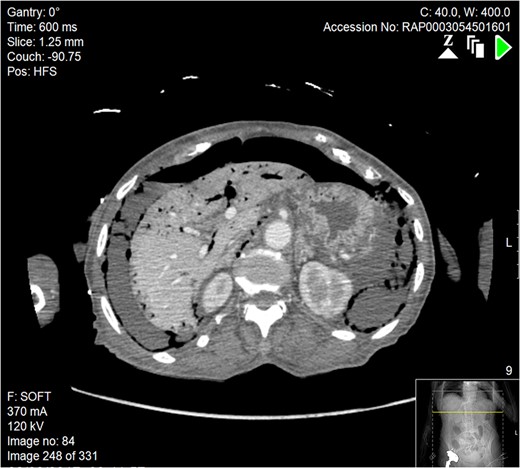

Subsequently a computerized tomography scan was performed of her chest, abdomen and pelvis (CTCAP), showing hepatic portal venous gas (HPVG), with visible air fluid levels (Fig. 1). There was a large amount of free air and free fluid within the abdomen and pelvis, highly suspicious for perforation (Fig. 2). There was also partial ischaemia of liver segment seven.

Axial section of abdominal CT scan. There is a significant quantity of free air and fluid within the abdomen, which can be seen adjacent to the liver, indicative of bowel perforation. Free air can also be seen in the portal venous system of the liver.